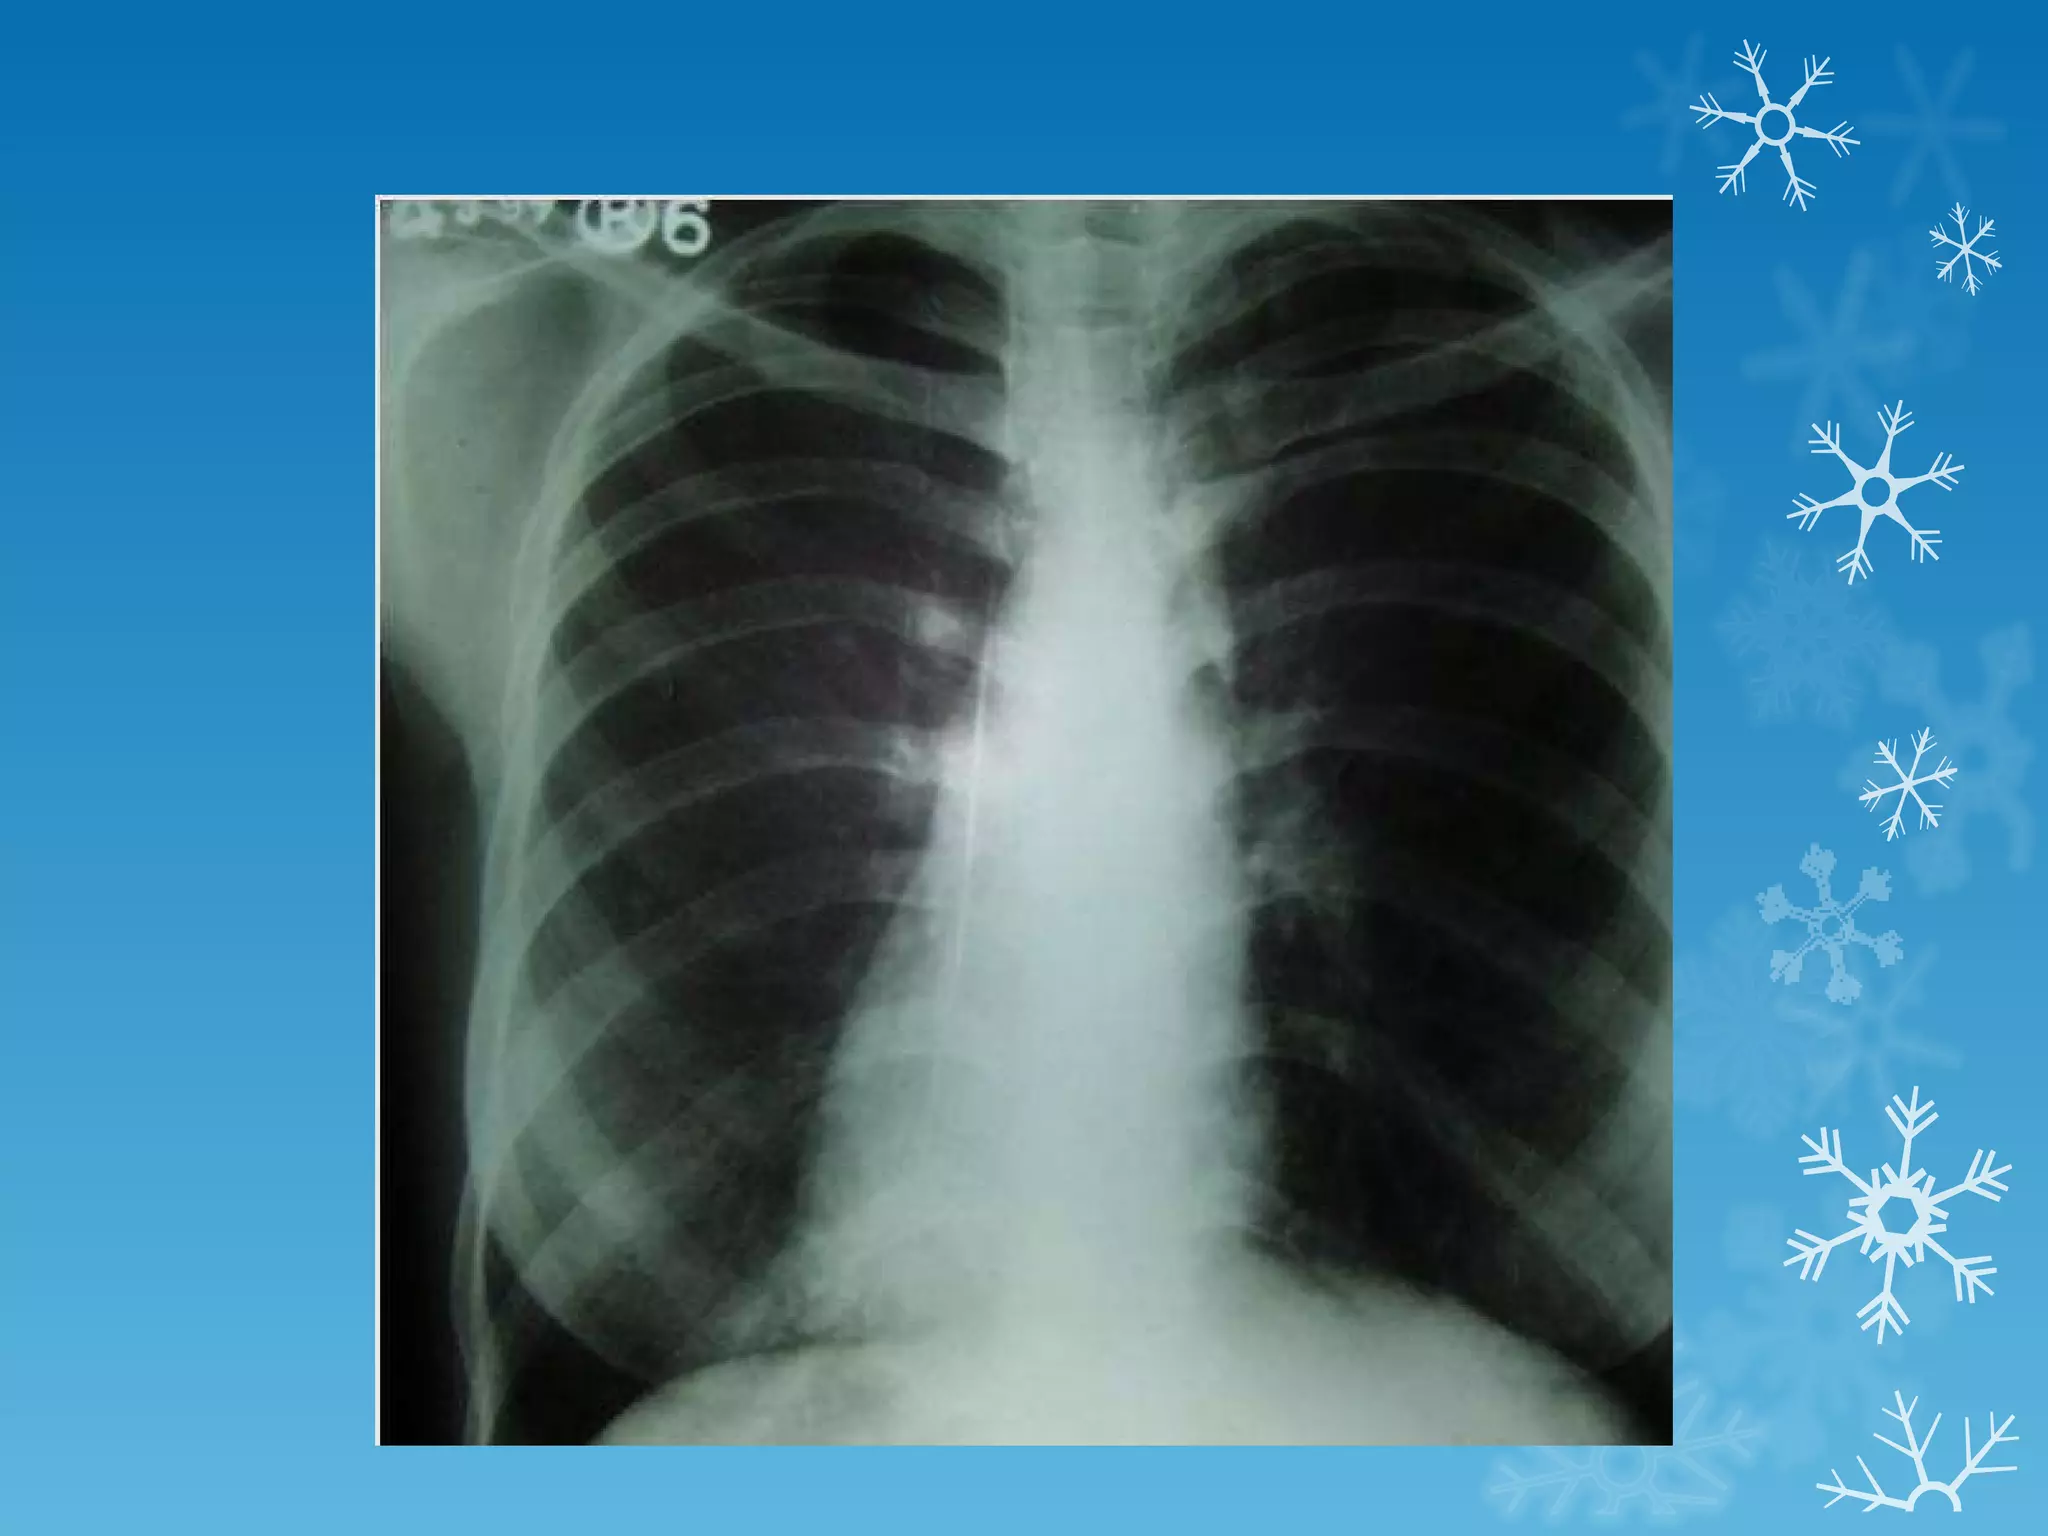

This document discusses chest x-ray interpretation and provides guidance on evaluating x-rays. It explains that tissue density determines how an x-ray beam penetrates, with denser tissues appearing whiter and less dense tissues appearing blacker. It also outlines different chest x-ray views and factors to consider like patient orientation, age, gender, and rotation. Abnormalities are described as appearing too white, too black, too large, or in the wrong place. The document stresses a systematic approach of identifying, localizing, describing lesions, and providing differential diagnoses.